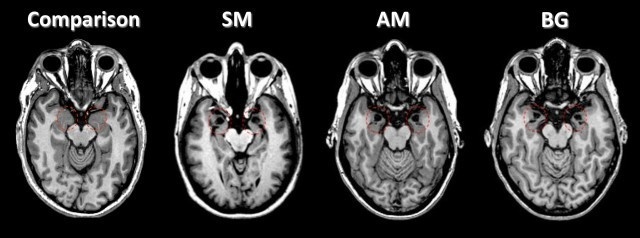

La paciente, una mujer de 40 años conocida como SM, presenta una condición extremadamente rara, denominada enfermedad Urbach-Wiethe, un trastorno que ocasiona grandes daños en la amígdala, un área cerebral con forma de almendra que está vinculada al temor. Desde que comenzara a sufrir esta enfermedad, cuando aún era una adolescente, la paciente no había vuelto a sentir miedo.

El equipo de la UI decidió probar con SM y otras dos pacientes cuya amígdala estaba dañada, su respuesta a una amenaza bien conocida. En este caso, se pidió a las participantes, todas mujeres, que inhalasen una mezcla de gases que contenía un 35% de dióxido de carbono. Este tipo de prueba constituye uno de los experimentos más comúnmente utilizados en laboratorio para inducir ataques de pánico breves, de una duración de entre 30 segundos y un minuto.